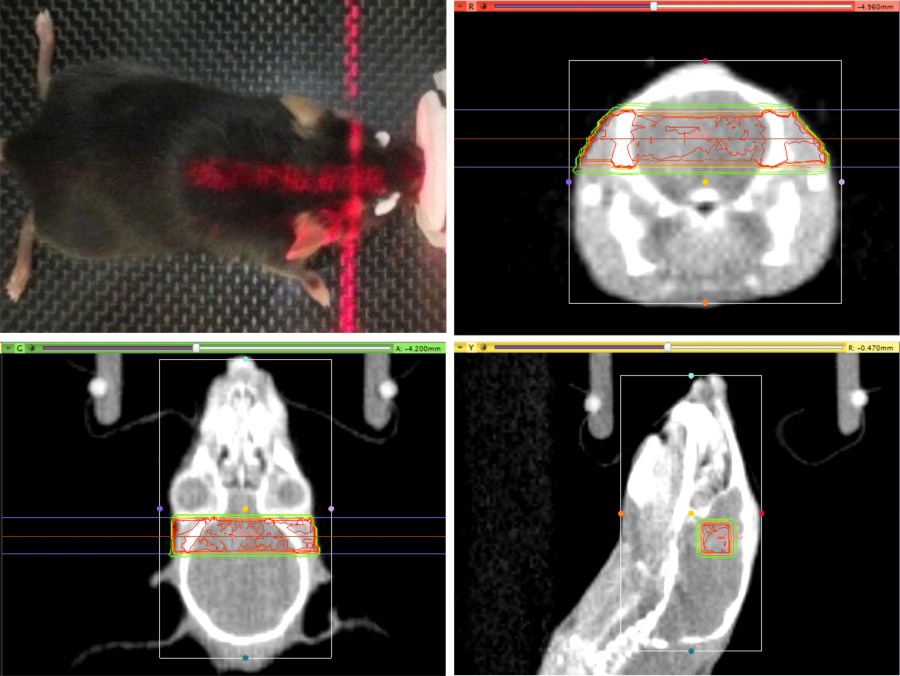

Radiotherapy in preclinical animal models

Radiotherapy is a central element of multimodal cancer treatment, which has experienced tremendous advancements in the recent years and decades. As such, the implementation of new imaging modalities, the improvement of treatment planning algorithms, the development of image-guidance techniques for dose administration, and the advent of new irradiation qualities have transformed radiotherapy into a versatile tool of high precision radiosurgery. In addition, biologically and immunologically motivated strategies to improve the radiotherapeutic outcome are leading to a constantly increasing number of novel combined-modality treatment approaches with molecularly targeted agents.

In order to evaluate the potential for clinical translation of these advancements, careful preclinical testing in appropriate models is absolutely indispensable.